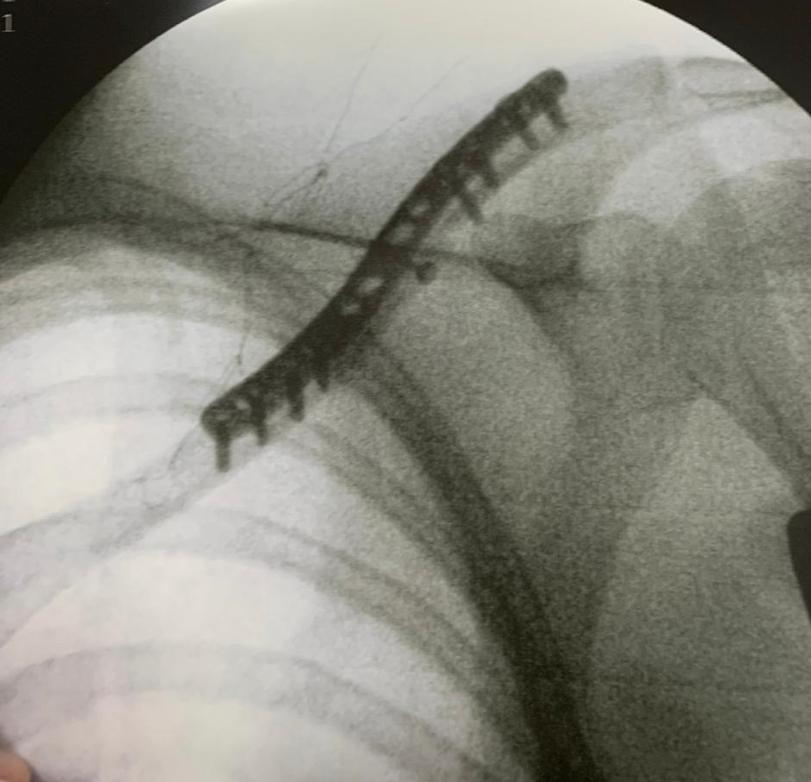

FRATURA DA CLAVICULAR

A clavícula é o osso responsável em ligar o esqueleto axial ao membro superior. A fratura deste osso é comum, e acomete principalmente homens jovens com idade abaixo de 20 anos, após uma queda sobre o ombro. A maioria (80-85%) das fraturas da clavícula ocorrem no terço médio. Geralmente apresenta inchaço, com arroxeado local de pele e geralmente com a movimentação se ouve pequenos estalos Essas fraturas, quando com pouco desvio, podem ser tratadas conservadoramente com imobilização. Em casos de cirurgia existem 2 opções principais: colocação de placa e parafusos ou uma haste intramedular.